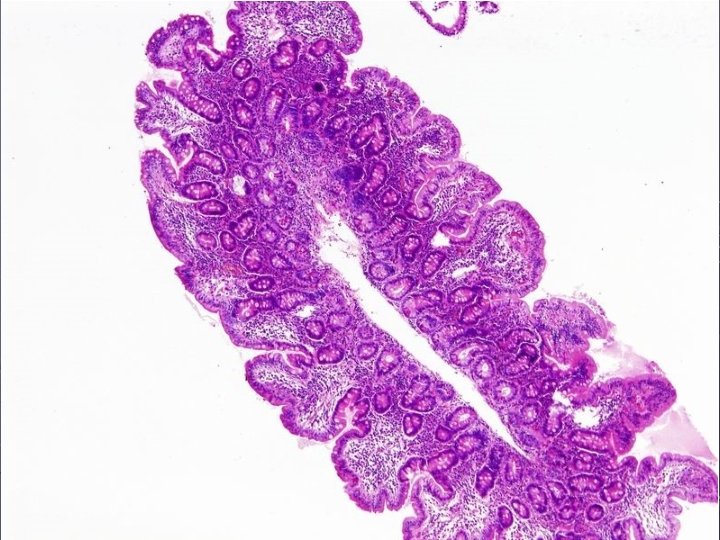

Histologické nálezy (Marsh): Spectrum změn od IEL (intraepiteliální lymfocyty) po atrofii O I. III. normální struktura bez zmnožení IEL normální struktura + zmnožení IEL (více než 30, 40 ly/100 epitelií), CD 3, 2 IEL, hyperplazie krypt, (protažení, větvení) IEL, hyperplazie krypt, zánětlivá celulizace, vilózní atrofie 3 stupně vilózní atrofie: n A parciální n B subtotální n C totální

Hodnocení nálezů: M I. u dermatitis herpetiformis M II. po léčbě: zlepšení M III. - jednoznačná celiakie bez léčby: nejednotný názor: nesplňuje morfologická kriteria Ale: zlepšení po bezglutenové dietě morfologicky po dietě M I. Nebo M O většinou + genetika